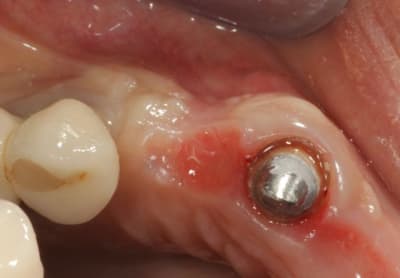

Grosse perte osseuse au niveau de la 23, ROG avec Bio-Oss et autogène dans un rapport 50/50, le tout recouvert pas une BIo-gide maintenu avec de pin's.

Désolé pour le retard, je vais essayé de répondre à tout le monde, mettre un implant et faire une ROG de façon predictible dans un cas comme ça c'est impossible, la photo pré-op c'est la dernière ( je ne sais pas pourquoi nonol m'a inversé l'ordre ), à noter que j'ai fait ce design d'incision car 24 et 25 sont des implants et je ne voulais justement pas me retrouver avec une récession.

J'ai utilisé du BIo-Oss et de l'autogène prélevé avec un scraper à la mandibule, le tout recouvert par une Bio-Gide maintenu par des pin's, suture avec du Gore Tex ( e-PTFE ) et du Cytoplast (PTFE )